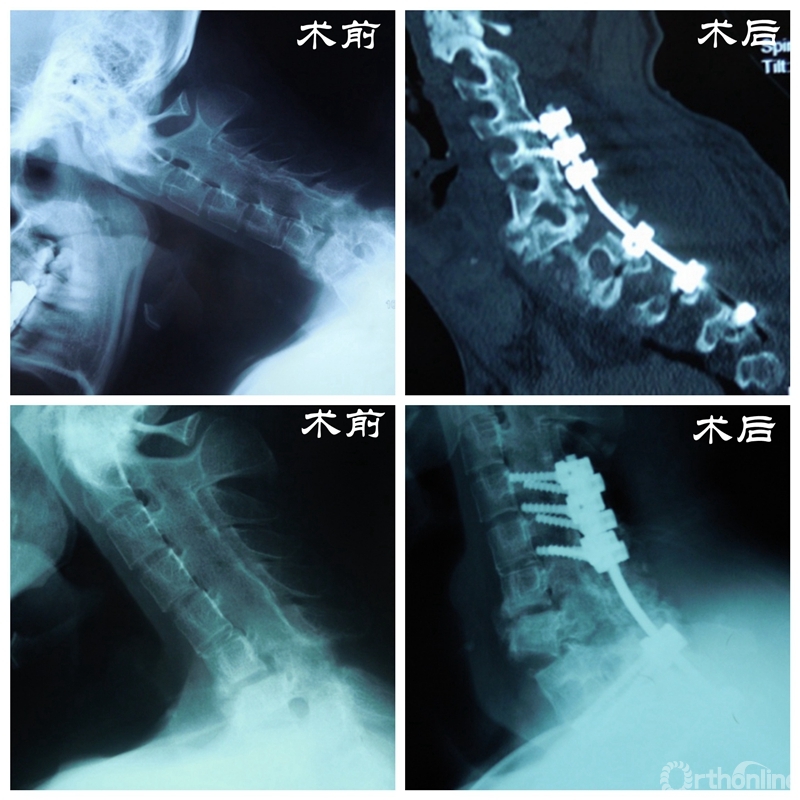

2014年初,丁文元教授像往常一样来到门诊,等在诊室门口的一个小伙子吸引了他的注意。这个小伙子由母亲带着前来就诊,身材高大壮实,但始终不曾抬起头来。经过周密的检查和问诊,丁文元教授得知这个小伙子28岁,名叫大帅(化名),患有强制性脊柱炎颈胸段鹅状畸形,此时也明白了他始终不抬头的原因。

患者资料

门诊结束后,丁文元教授立刻带领团队成员开始查阅大量相关文献,为大帅的手术进行充足的准备和周密的计划。幸运的是手术很顺利,术后复查各项指标恢复良好,大帅的头也抬起了来了,脸上洋溢着久违的笑容,这给了医生和患者家庭极大的信心。